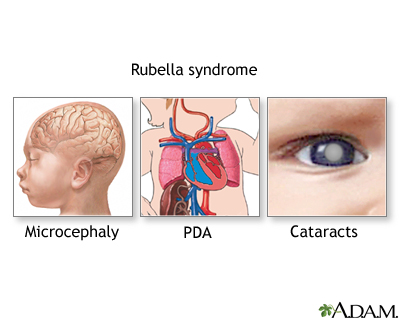

Rubella is caused by a virus. The infection leads to a mild illness that includes a rash, enlarged lymph nodes, and sometimes a fever. If a pregnant woman is infected during her first trimester, her baby has an 80% chance of developing birth defects, including heart abnormalities, cataracts, deafness, and learning disabilities.